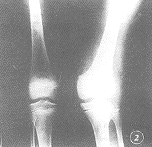

1.軟骨發育不良 表現為上下肢長骨縮短遠側節段比近側節段嚴重,故膝與肘以下的長骨更短對軀幹的影響不大故形成侏儒。脛骨近側端擴張,變尖,骨骺發育差並偏內側滑移。在脛骨近側乾骺端內側有骨疣突出腓骨短與軟骨發育不全不同,小腿呈現膝外翻髕骨同時向外移位。橈骨頭常脫位,指骨很短,這是由於指骨無骨化中心。腕骨和尺橈骨可融合;股骨和肱骨呈弓形短而厚;肋骨短故胸廓可長而窄頭顱正常多指是典型特徵多見於尺側橈側多指較少見。

本病的主要矮短特點是膝部以下的脛腓骨和肘以遠的尺、橈骨短縮所造成的。故根據臨床外觀及X線檢查一般鑑別並不困難。

脊柱四肢可行X線檢查,可見膝肘部以下長骨短縮明顯。